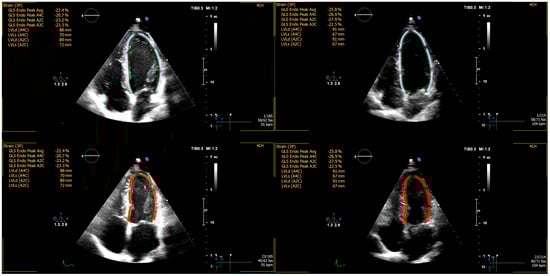

2.2. Echocardiographic Imaging and Analysis

| EF, % | 64.0 ± 3.0 | 63.4 ± 3.0 | 0.500 |

| GLS | −24.8 ± 1.7 | −22.3 ± 1.7 | 0.262 |

| Δ GLS | −1.7 ± 1.5 | 0.2 ± 1.5 | 0.652 |